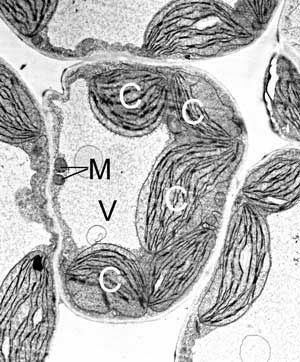

Mediziner können sich freuen: Die Fahndung nach Proteinen, die bei Erbkrankheiten des Menschen eine Rolle spielen, gleicht nicht länger der Suche nach einer Nadel im Heuhaufen. Sie erhält vielmehr gezielte Unterstützung durch eine breit angelegte Datenbankrecherche: Forscher des Max-Planck-Instituts für Züchtungsforschung (MPIZ) in Köln haben per Computer Gene beziehungsweise die dazugehörigen Proteine identifiziert, die wahrscheinlich eine Rolle bei Erbkrankheiten wie der Mukoviszidose spielen. In der Juli-Ausgabe des internationalen Fachmagazins "Trends in Genetics" beschreiben die Biologen Dario Leister und Erik Richly vom MPIZ, sowie der britische Mediziner Patrick F. Chinnery von der Medical School in Newcastle upon Tyne die Methode, mit der sie "verdächtige" Gene aus der Masse des menschlichen Erbguts gefischt haben. Das Ergebnis sind 100 Proteine, die in den "Kraftwerken der Zellen" - den Mitochondrien - sowohl beim Menschen als auch bei Pilzen, Pflanzen und Insekten vorkommen.

Bisher konzentrierten sich die Kölner Forscher vor allem auf Chloroplasten, die Solarzellen der Pflanzen. Für die Modellpflanze Arabidopsis etwa stellten sie fest, welche Gene Produkte, also Proteine bilden, die in die Chloroplasten wandern. Dieser "Spürsinn" rief den Mediziner Chinnery auf den Plan. Zu seinem Arbeitsgebiet gehört es, den Zusammenhang zwischen menschlichen Erbkrankheiten und Mitochondrien zu klären. Weltweit suchen Wissenschaftler mit den unterschiedlichsten Methoden nach den Mitochondrien-Proteinen, weil sie bei vielen Krankheiten eine Schlüsselrolle inne haben. Doch keine dieser Methoden hat bisher die Frage vollständig beantworten können, welche Proteine in den Zellkraftwerken arbeiten und wie sich diese bei ganz unterschiedlichen Lebewesen unterscheiden.

Gemeinsam mit dem Briten durchsuchten die Kölner Pflanzenforscher artübergreifend das Erbgut nach solchen Genen, deren Produkte in den Mitochondrien zu finden sind. Der Hintergedanke dabei: Gene und deren Produkte, die sich im Laufe der Evolution bewährt haben, kommen in ganz verschiedenen Lebewesen vor, finden sich also in den Mitochondrien von Mensch und Mücke, Fisch und Fliege, Pilz und Pflanze. Für die Suche nach solch "alten" Bestandteilen nutzten die Wissenschaftler den Computer, mit seiner Hilfe identifizierten sie bestimmte Proteinabschnitte. Diese so genannten mitochondrialen Transitpeptide weisen den Proteinen den Weg Richtung Mitochondrien.